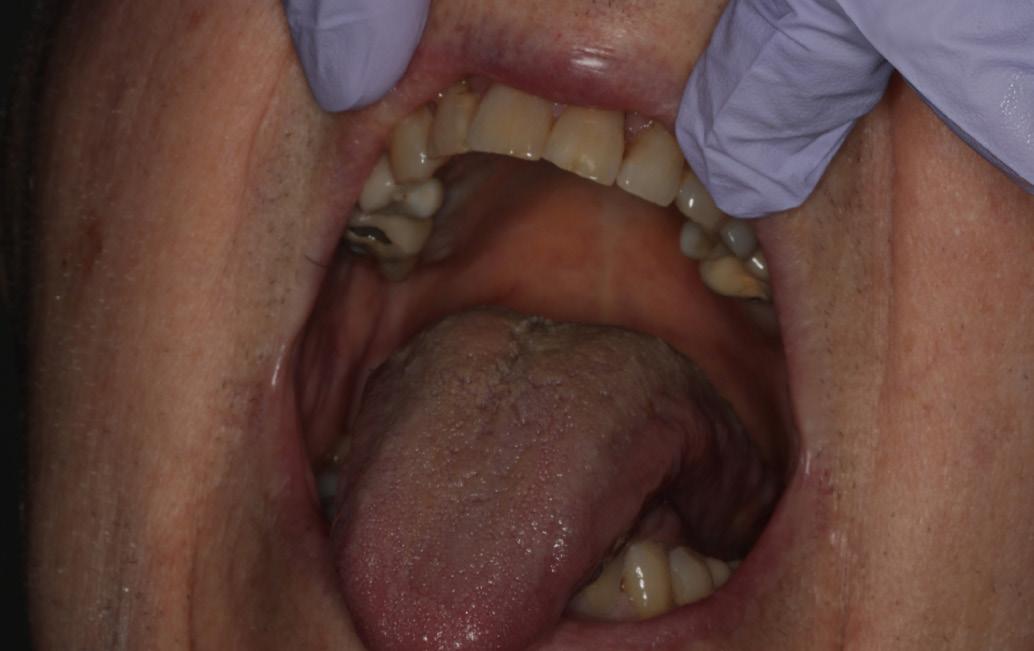

with a topical corticosteroid mouth rinse was continued. Within two weeks, the ulcers healed completely (Fig 2). Methotrexate was later resumed at the same dose with continued 5 mg folic acid daily, and no recurrence was noted at follow-up.

The patient’s general practitioner was consulted, and methotrexate was suspended for three weeks. Following this, resolution of the ulcers was noted (Fig. 2b). She was then prescribed dexamethasone mouthwash, which led to marked improvement of the lesions.

Complete resolution of ulcers within 2 weeks.

Marked improvement and healing noticed after discontinuing methotrexate for 3 weeks.